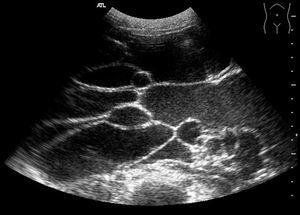

En la ecografía abdominal se apreciaba ocupación de prácticamente toda la cavidad peritoneal por una lesión predominantemente anecoica que presentaba tabiques finos, lisos, sin irregularidades ni engrosamientos murales (fig. 1).

Figura 1. Colección anecoica que presenta numerosos tabiques finos y regulares.